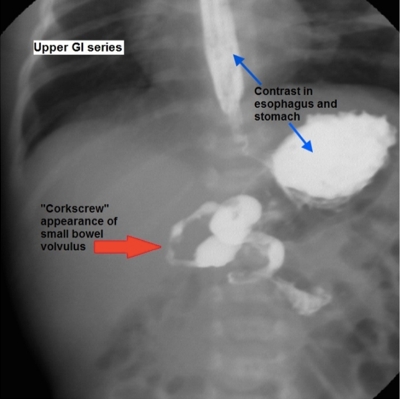

Back Muscles

The arrow points to a bilaterally symmetric structure that lies in close association to the vertebral body and vertebral transverse process. This is the psoas muscle, which originates from the anterior surface of the transverse processes and lateral surface of the vertebral bodies at T12-L5. Inferiorly (at around the level of the inferior ligament), the psoas muscle combines with the iliacus muscle(Choice B) to form the iliopsoas muscle, which functions in hip flexion. Intraabdominal or more distal infections can spread to these muscles (eg, psoas abscess) and cause abdominal pain, fever, and weight loss. HIV, intravenous drug use, and diabetes are risk factors for primary psoas abscess development.

(Choice A) The erector spinae (also shown in the image above) is a large muscle group of the back that courses longitudinally along the spinous processes. Bilateral contraction causes spine extension.